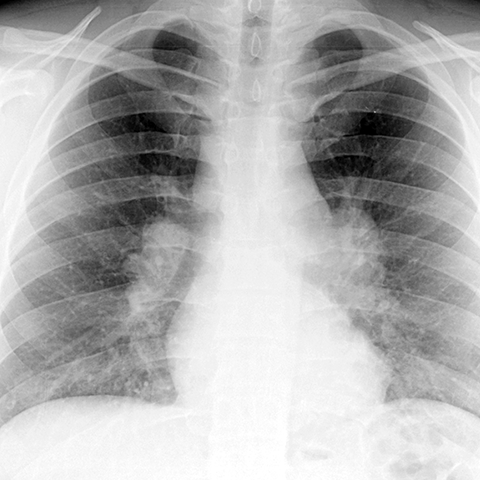

Hilar and Paratracheal Nodes in Sarcoidosis [1 of 3]